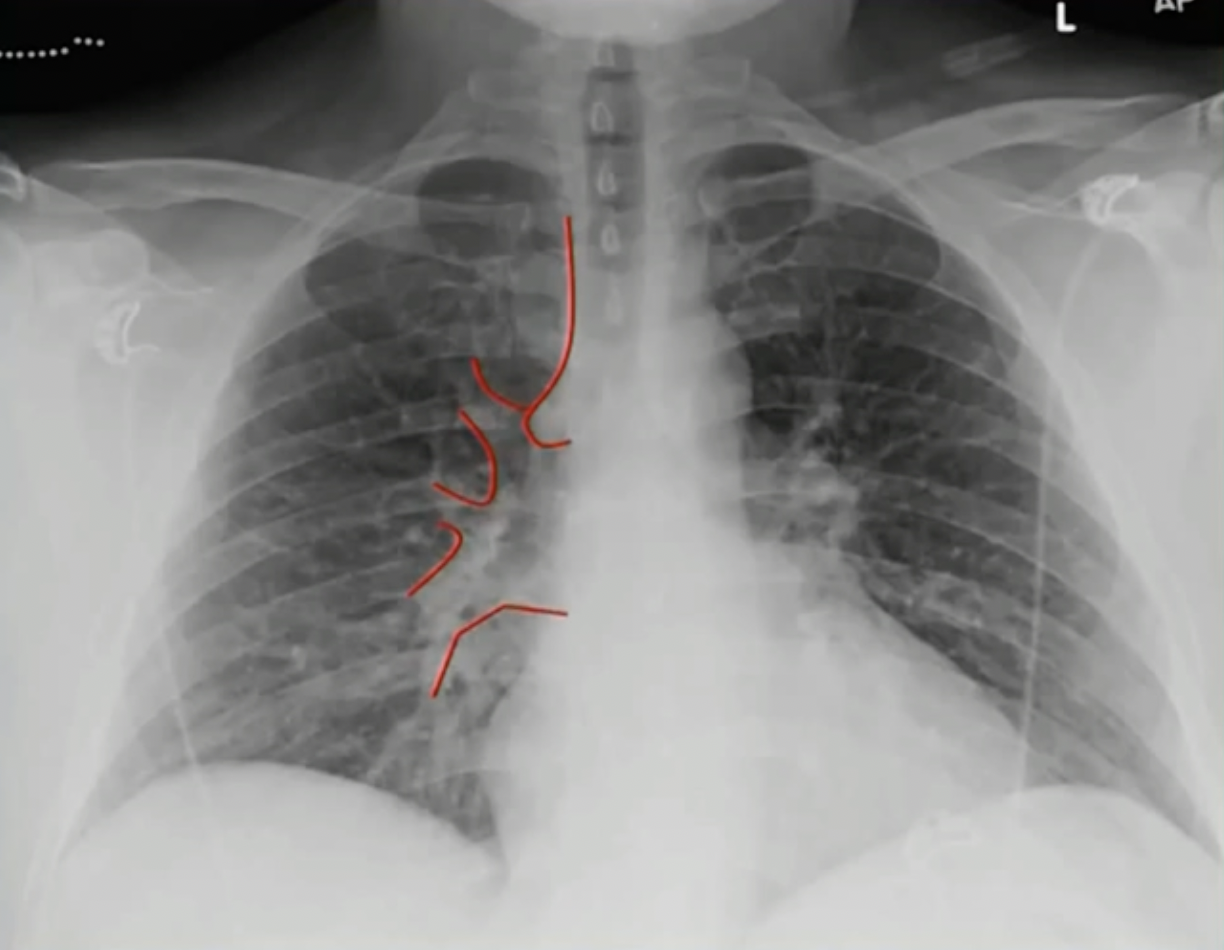

# 正位